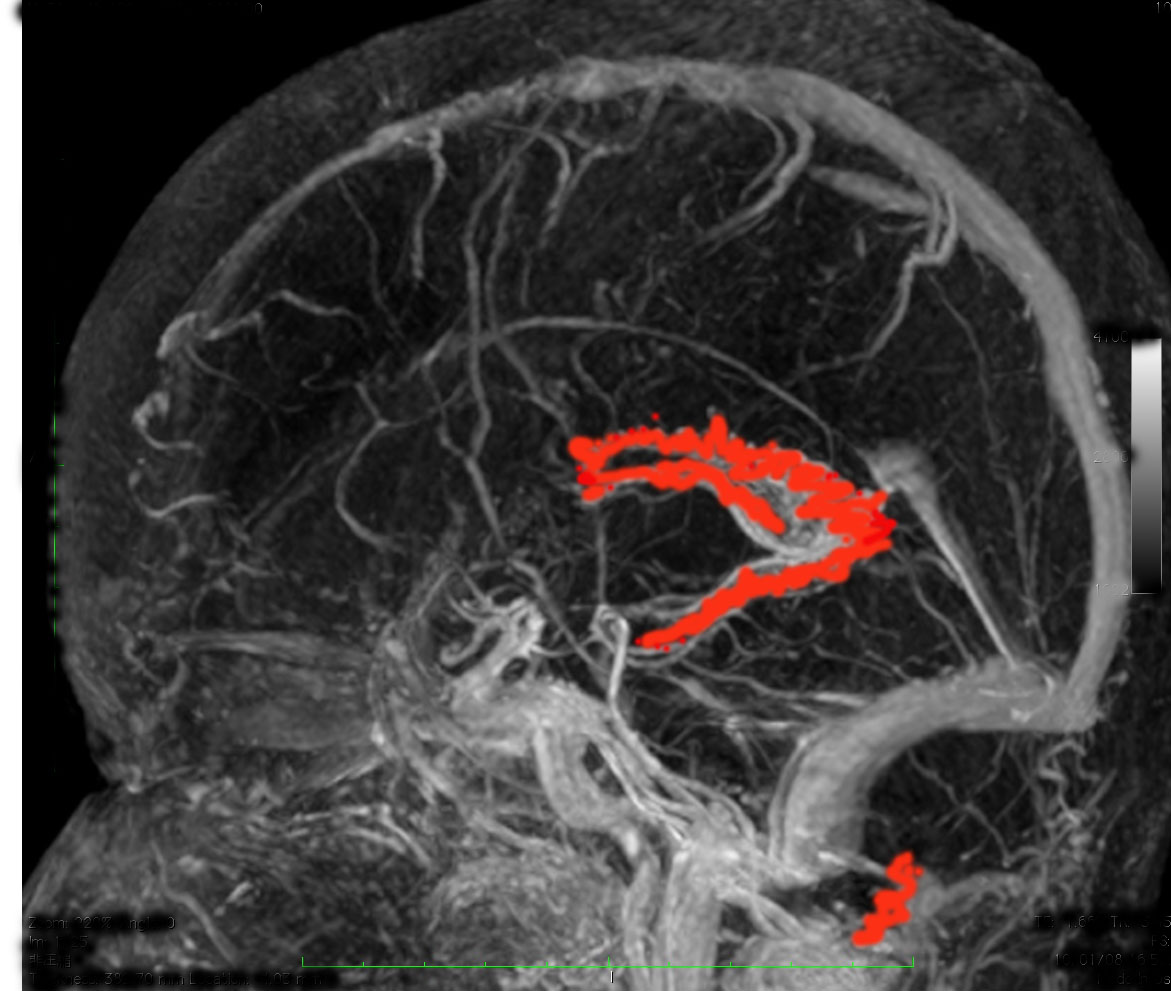

脳室内脈絡叢です(脳の静脈と一緒に描出しています)

正面から脈絡叢を見たところと左横から見たところ

- 髄液は脈絡叢(赤く塗ったところ)で作られます。

- 脈絡叢は側脳室と第3脳室と第4脳室にあります。下の方に離れているのが第4脳室のものです。

- 髄液 CSF cerebrospinal fluid は,くも膜顆粒 arachnoid granule から吸収されて,太い静脈に入り,心臓まで帰って行きます